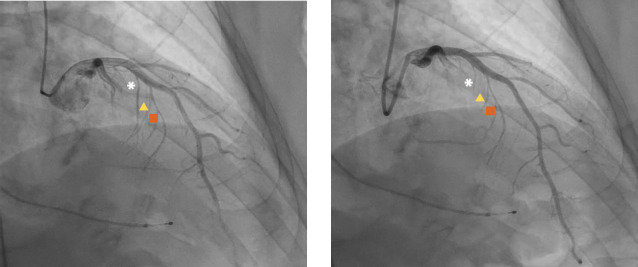

尽管肥厚型心肌病的治疗取得了长足的进步,但晚期心力衰竭仍然是导致这类患者发病的主要原因。这篇叙事性综述介绍了一名接受酒精房间隔消融术的肥厚型梗阻性心肌病患者的病例,并以此为框架讨论肥厚型心肌病的现代疗法。目前的治疗方法包括新旧药物、外科手术和程序干预,以缓解机械性梗阻。目前有几种很有前景的缓解梗阻的新方法正处于研发初期。

Despite substantial advances in the management of hypertrophic cardiomyopathy, advanced heart failure remains a major cause of morbidity in this patient population. This narrative review presents the case of a patient with hypertrophic obstructive cardiomyopathy who underwent alcohol septal ablation to frame a discussion of modern therapies for hypertrophic cardiomyopathy. The current treatment landscape includes medications, both old and new, and surgical and procedural interventions to relieve mechanical obstruction. Several promising new modalities for relieving obstruction are in the nascent stages of development.